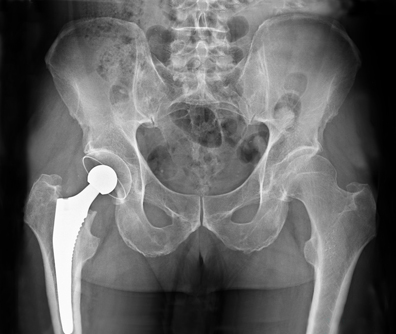

Changement de prothèse totale de hanche

La mise en place d’une prothèse de hanche est généralement réalisée suite à une usure arthrosique de cette articulation ou suite à une fracture. Malheureusement, les contraintes mécaniques sur cette prothèse entraînent des phénomènes d’usure au bout de nombreuses années. Si la prothèse devient douloureuse, un descellement peut être suspecté qui conduira logiquement à un changement d’une ou plusieurs pièces de la prothèse.

C’est généralement une intervention plus lourde que la mise en place de votre prothèse initiale. Elle consiste en l’ablation de la prothèse usée ou infectée et à son remplacement par une autre prothèse pouvant se fixer correctement sur l’os abîmé. Ce remplacement peut se faire d’emblée ou secondairement s’il s’agit d’une infection.

Les différents types de descellement sont très variables et peuvent toucher le fémur et/ou le cotyle. C’est pourquoi les interventions de reprise sont toutes différentes mais généralement la taille de la prothèse mise en place sera supérieure à votre ancienne prothèse.

Il arrive également qu’une seule partie de la prothèse soit changée en fonction de l’usure de celle-ci.

Certains gestes complémentaires sont parfois nécessaires pour enlever la prothèse et fixer correctement la suivante comme une ostéotomie fémorale d’exposition, l’apport de greffons osseux ou la pratique d’une ostéosynthèse par plaque, vis ou cerclage.